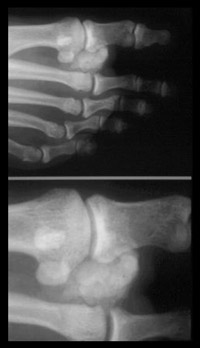

There are two types of hammer toe:

Fixed - due to fusion and calcification of the joints or extremely tight tendon/weak muscle – which can lead to fused joints

Mobile - often due to a plantar-flexed first ray (low ball of foot striking the ground first causing the outer four toes to reach downwards searching for the ground

'Mallet toe,' and 'claw toe' are similar conditions affecting the toe joints. Treatment is also similar but as always requires tailoring to the individual.

This condition often leads to corns (pressure sores) in the toe joints and tips.

We build in accommodating cushioning and toe height and metdomes as necessary to alleviate pressure and encourage correct balancing of the forefoot.